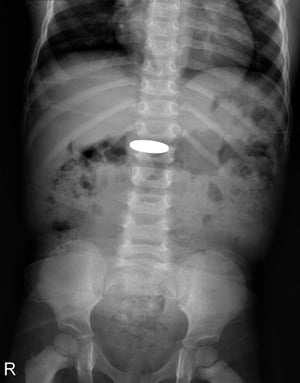

Sinar-x ini menunjukkan koin yang ditelan oleh anak kecil.

PERPUSTAKAAN FOTO DU CANE MEDICAL IMAGING LTD/SCIENCE